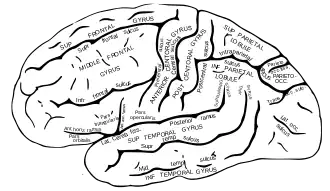

Within the brain, visual stimuli are processed along many different neural circuits. Due to the evolutionary importance of being able to recognize faces and associate information with others based on this recognition, humans have evolved a distinct neural circuit for the processing of facial stimuli.[6] Since the discovery of this distinct circuit, the anatomical structures involved have been studied in depth.[7] The initial processing of visual stimuli occurs in the prefrontal cortex (PFC), postparietal cortex (PPC), and precuneus. The stimuli are then identified as being facial and more refined processing occurs within the fusiform face area (FFA),[8] the occipital face area (OFA), and the face-selective region of the superior temporal sulcus (fSTS). The FFA serves low level tasks, such as distinguishing details between similar well-known objects. The OFA and fSTS serve higher level processing tasks, such as connecting a person's identity to their face and processing emotions based on the arrangement of facial features, respectively. Once facial stimuli have been processed, they are then encoded into memory. This involves many brain structures including the medial temporal lobe (MTL), and the hippocampus. Storage and retrieval of these memories involves the same regions of the FFA, PFA, and PPC that performed the initial processing tasks.[9]